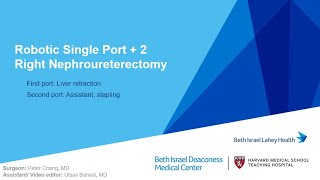

Robot-Assisted Nephroureterectomy and Bladder Cuff Excision Robotic SP +2 Right Nephroureterectomy

Robotic SP +2 Right Nephroureterectomy Robotic assisted nephroureterectomy: a three stage approach

Robot-Assisted Nephroureterectomy and Bladder Cuff Excision Robotic SP +2 Right Nephroureterectomy

Robotic SP +2 Right Nephroureterectomy Robotic assisted nephroureterectomy: a three stage approach